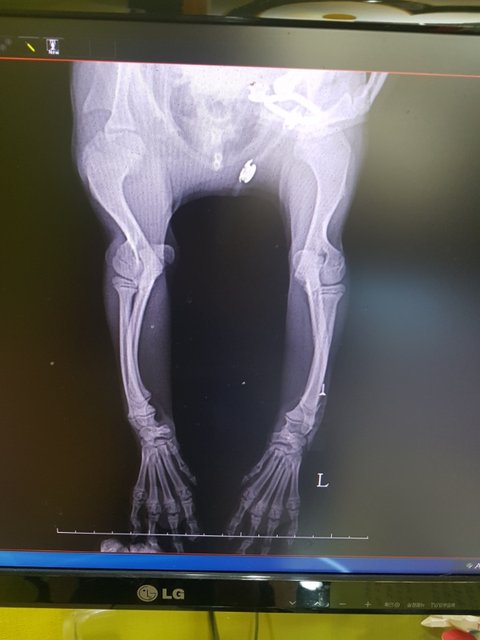

아이다리 좀 봐주세요

영양부족인 구루병일까요..

아님 선천적인 기형인걸까요..

문제의 다리는 영양결핍으로 인한 구루병이라고 합니다

아직 성장판이 열려있어 잘 먹이면 좋아질꺼라고 합니다